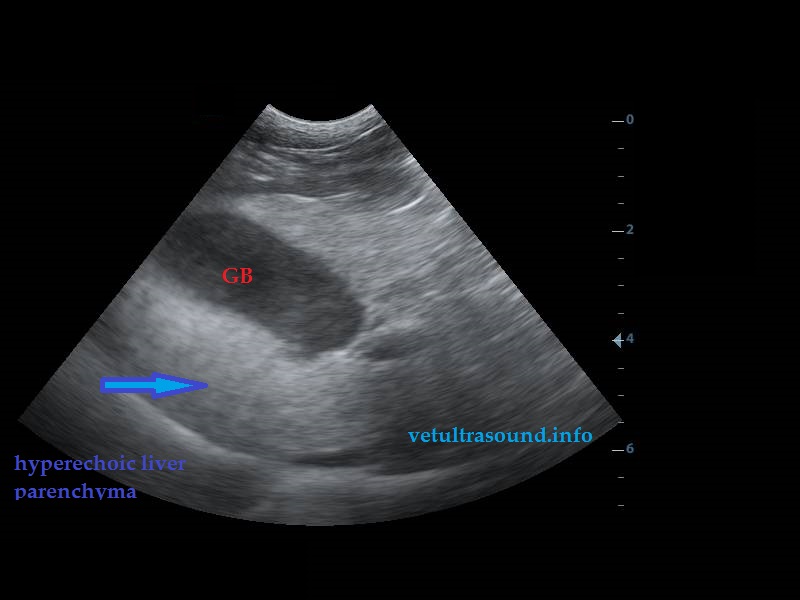

Increased echogenisity of the liver. There was no clear distinction between liver’s parenchyma and the portal’s vein wall.(pic1)

Έντονη αύξηση της ηχογένειας του ηπατικού παρεγχύματος. Δεν ήταν δυνατή η διαφοροποίηση του ηπατικού παρεγχύματος από το τοίχωμα της πυλαίας φλέβας.(pic1)